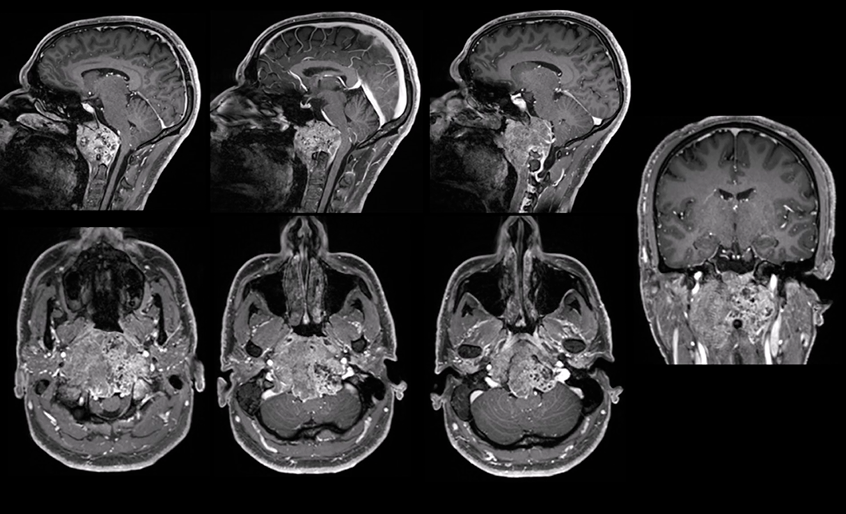

術(shù)前:腫瘤體大,廣泛累及顱底結(jié)構(gòu),侵蝕斜坡、鞍內(nèi)鞍上、海綿竇區(qū),包裹右側(cè)頸內(nèi)動脈。腫瘤向上推擠視神經(jīng)、視交叉,到達三腦室底部;向后上方推擠腦干和基底動脈,部分腫瘤邊緣與腦干分界欠清。

2023年5月,福教授應(yīng)邀訪問蘇州大學(xué)附屬獨墅湖醫(yī)院(蘇州市獨墅湖醫(yī)院),蘇先生抓住了這個機會,咨詢福教授能否為自己手術(shù),在經(jīng)過一系列評估以及術(shù)前緊急補充激素等措施,2023年5月15日,INC法國福教授為蘇先生做了四次開顱手術(shù),在術(shù)中,福教授聯(lián)合應(yīng)用顯微鏡和內(nèi)鏡,運用的“筷子手法”,術(shù)后當(dāng)晚核磁顯示腫瘤已基本全切。這對夫妻是幸運的,在這場風(fēng)險較大、具挑戰(zhàn)的手術(shù)中重獲新生。

術(shù)后:手術(shù)順利,術(shù)中將鞍上鞍內(nèi)、海綿竇區(qū)、三腦室腫瘤切除